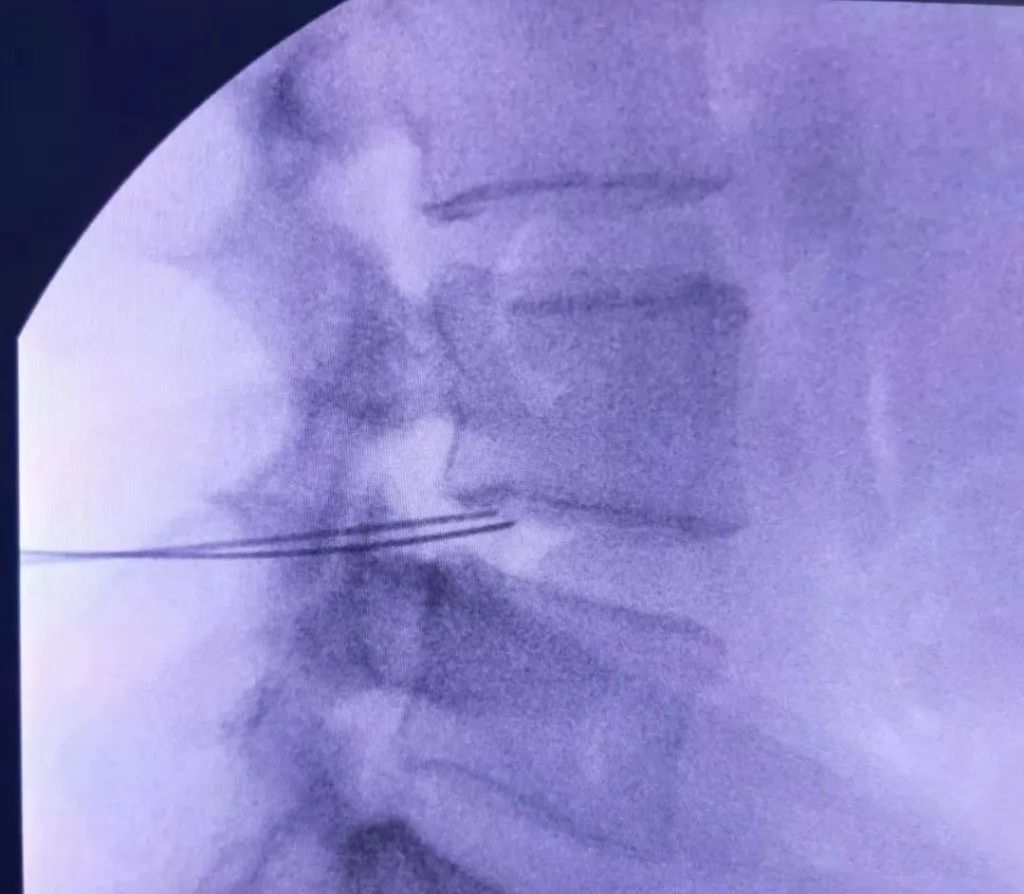

患者青年男性,以腰部疼痛为主诉入院。患者诉腰部疼痛,久坐及长时间行走时疼痛明显,平卧时疼痛减轻,夜间加重。患者腰椎CT未见明显腰椎间盘突出,但腰椎磁共振示L4-5椎间盘退变明显,诊断椎间盘源性腰痛。保守治疗只能缓解部分疼痛症状,不能解除引起腰痛的直接原因,可以进一步行腰椎间盘射频消融术治疗。

上图:腰椎磁共振示L4-5椎间盘突出不明显,但退变明显,行C臂X线引导下L4-5椎间盘双侧射频消融术

X线引导下L4-5椎间盘双侧射频针置入

正侧位示位置准确